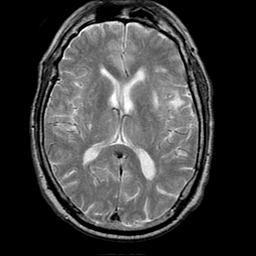

Meningioma, MR Study #1 -- Slice #10

[Home][Help][Clinical] Slice 10